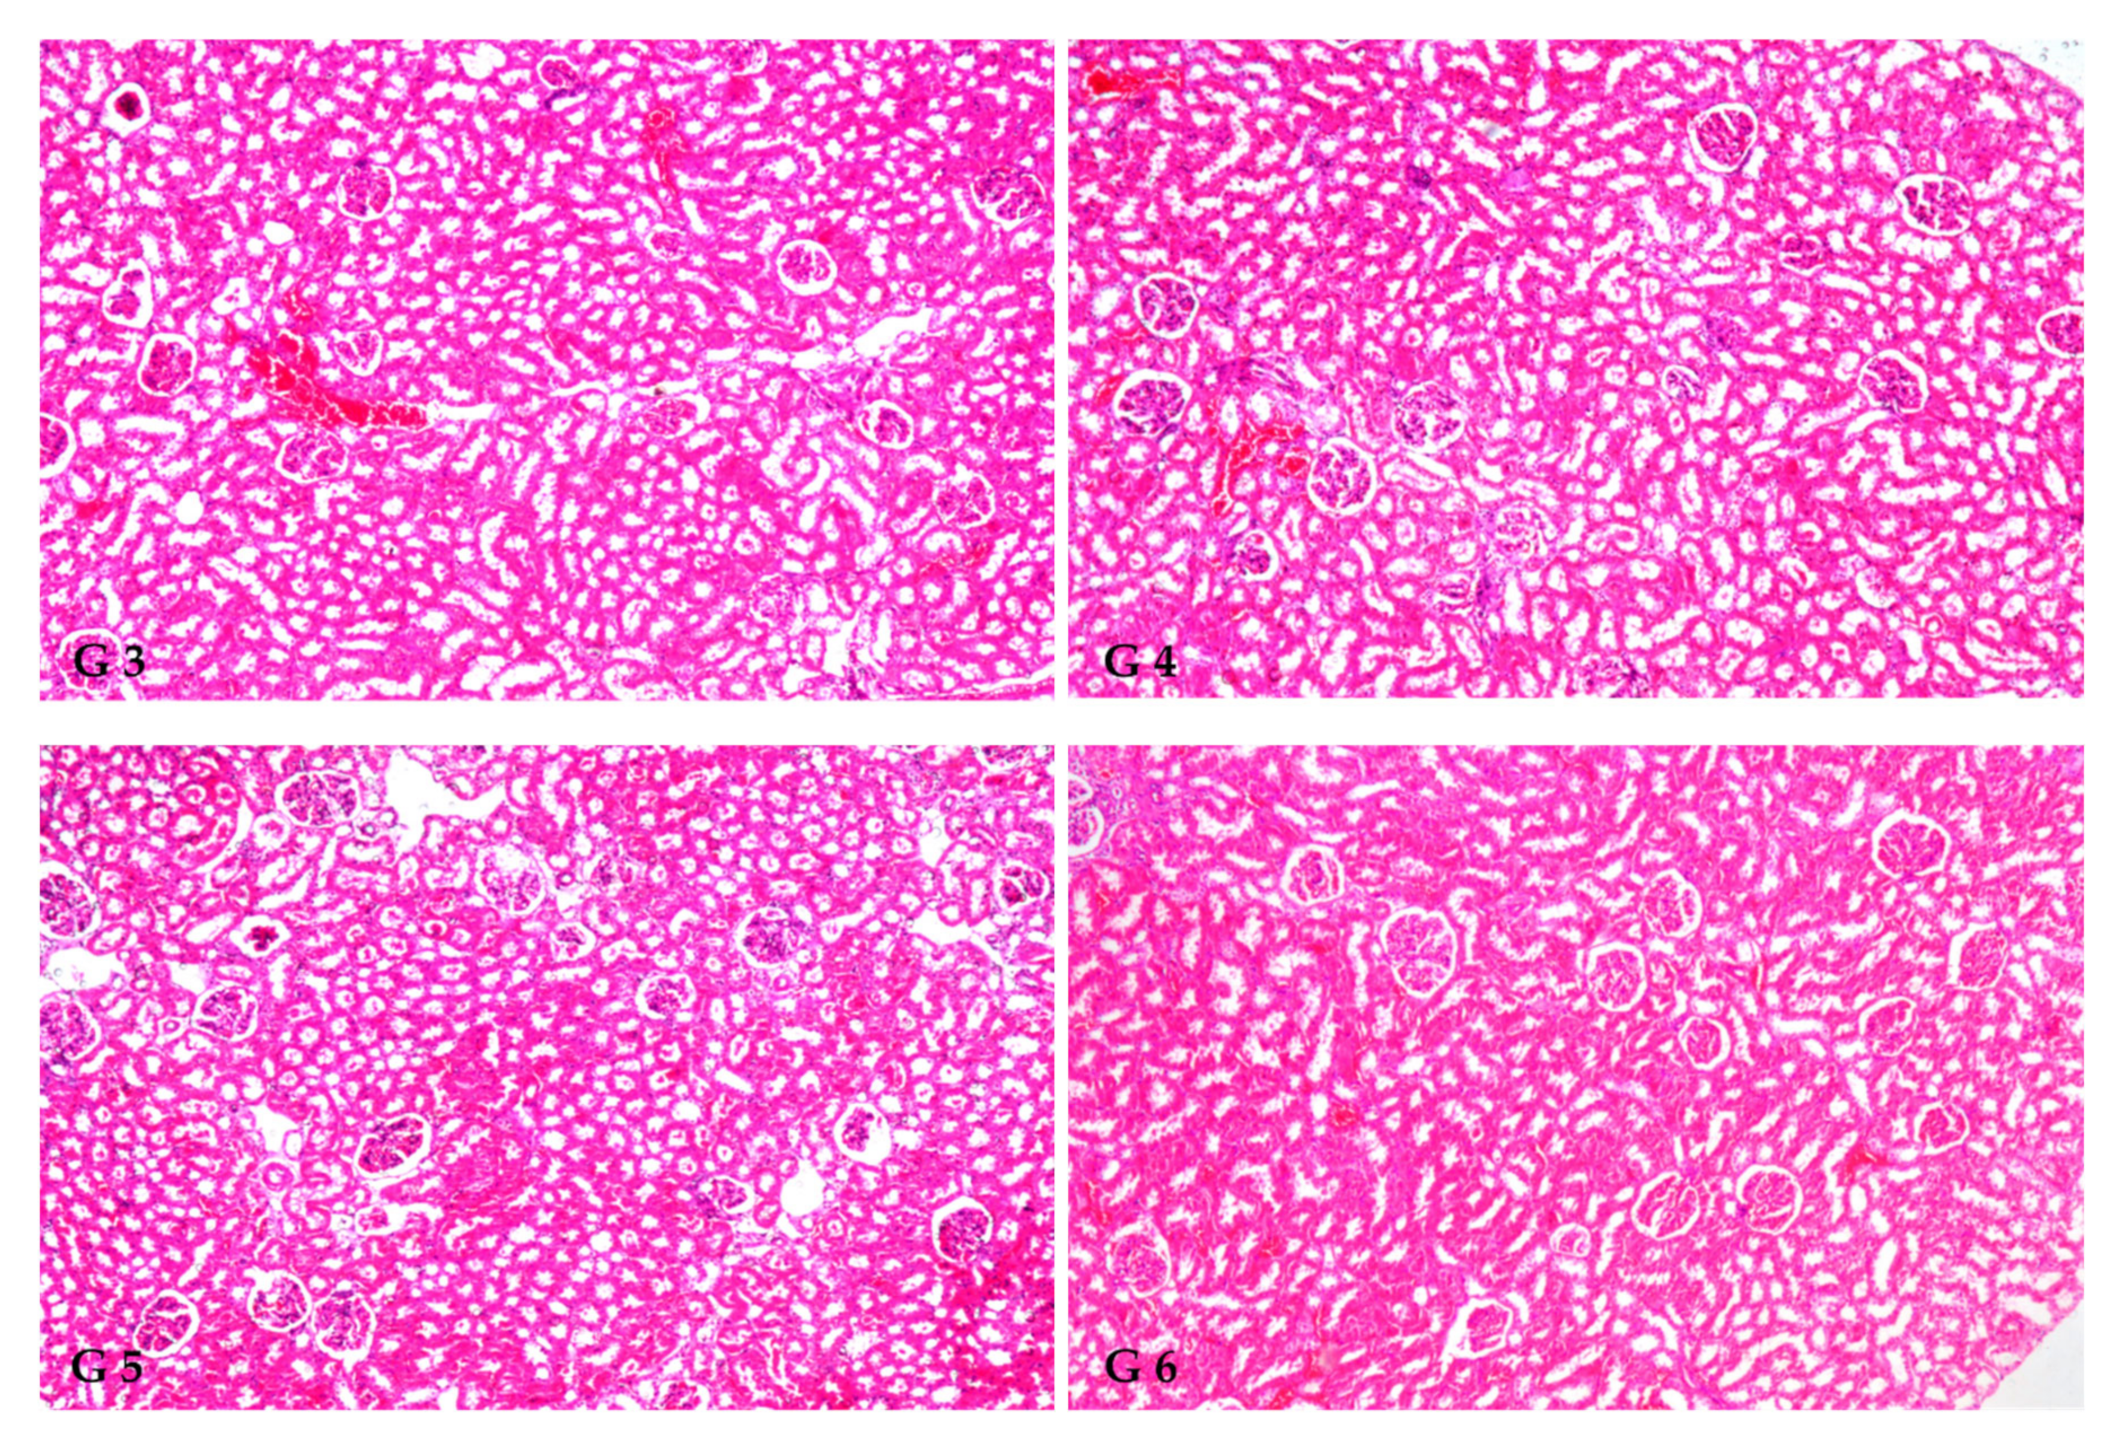

The histopathology confirmed the biochemical findings, as currently remarked. Figure 1 demonstrates the histological alterations in rat kidneys of treated rats treated with FS and FSS extracts. In this study, the kidneys of the control group (GI) had normal glomeruli and tubules at the cortex (Figure 1, G1). The histoarchitecture of the CCl4-treated rats (G2) showed focal inflammatory cell infiltration at the cortex surrounding the glomeruli and blood vessels and between the tubules (Figure 1, G2a). There was also focal fibrosis with atrophy and obliteration of the tubules with dilatation of the blood vessels at the cortex (Figure 1, G2b). The corticomedullary portion showed focal hemorrhages between the obliterated tubules (Figure 1, G2c) and focal cystic dilatation with flattened lining epithelium in others (Figure 1, G2d). Eosinophilic cast formation was detected in the lumen of the cystic tubules at the corticomedullary adjacent to the focal fibrosis (Figure 1, G2e). In G3, when 300 mg kg−1 aqueous extract of FS was given, congestion was observed in the cortical blood vessels (Figure 1, G3). However, administrating 600 mg kg−1 FS aqueous extract (G4) and both 300 and 600 mg kg−1 FSS alcoholic extract, as marked in (G5 and G6), respectively, showed no histopathological alteration as recorded in (Figure 1, G4, G5, and G6).

Figure 1.

Histopathological findings in rat kidneys treated by FS and FSS extracts along with CCl4 nephrotoxicity induction (X16 and X40). GI: Show normal histological structure of the glomeruli and tubules at the cortex, as recorded (G1). The histoarchitecture of the CCl4-treated rats (G2) showed focal inflammatory cell infiltration at the cortex surrounding the glomeruli and blood vessels as well as between the tubules (G2a), focal fibrosis with atrophy and obliteration of the tubules with dilatation of the blood vessels at the cortex (G2b), corticomedullary portion showed focal hemorrhages between the obliterated tubules (G2c), focal cystic dilatation with flattened lining epithelium in others (G2d), and eosinophilic casts formation was detected in the lumen of the cystic tubules at the corticomedullary adjacent to the focal fibrosis (G2e). G3 (300 mg kg−1 aqueous extract of FS) shows congestion in the cortical blood vessels (G3). In (G4) (600 mg kg−1 FS of aqueous extract), (G5, 300 mg kg−1 of FSS alcoholic extract), and (G6, 600 mg kg−1 of FSS alcoholic extract) showed no histopathological alteration as recorded in (G4, G5, and G6), respectively.

Histopathological kidney findings are congruent with biochemical estimates. CCl4 injection (G2) induced inflammation around glomeruli, blood arteries, and tubules. Dogukan et al. [113] observed similar histopathological alterations in the renal tissue of rats in response to CCl4. Histological alterations may also be produced by functional overloading of nephrons, leading to renal failure [86] and/or free radical production via CCl4 metabolism [114,115]. FS and FSS extracts help restore the kidney from the destructive effects of CCl4. This may be due to FS and FSS (as potent antioxidants) acting on reactive oxygen species (ROS) induced by CCl4 [116]. The phenolic components in F. vulgare extracts have an antioxidative role and free radical scavenging properties, which allows them to reduce CCl4-induced acute nephrotoxicity [52]. Our results are consistent with other researchers who found that plant extracts with varying molecular compositions have pharmacological effects by restoring normalcy after CCl4 abuses were introduced [52,117].